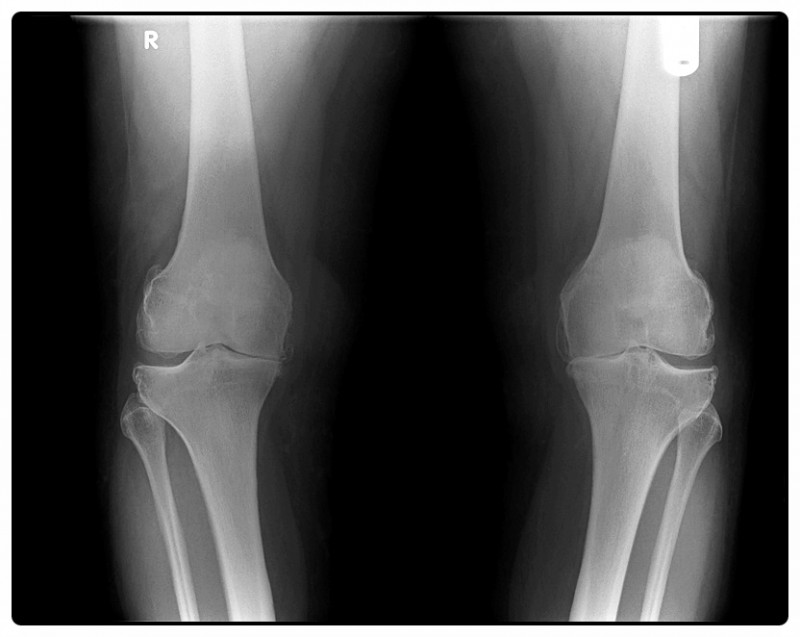

수술은 잘 끝났는데 왜 아직 아플까요?

무릎 수술은 손상된 구조를 복원해 통증의 원인을 제거하는 과정입니다.

하지만 수술로 인한 절개, 고정, 그리고 일정 기간 움직임의 제한은 근육 약화와 관절의 경직을 불러올 수 있습니다.

즉, ‘고쳐졌지만 아직 굳어 있는 상태’라고 할 수 있죠.

예를 들어, 전방십자인대(ACL) 수술 후 다리를 오랫동안 고정하면 허벅지 앞쪽 근육이 빠르게 위축됩니다.

근육의 힘이 약해지면 관절이 제자리를 잡지 못해 무릎 주변에 부담이 집중되면서 통증이 다시 생기기도 합니다.

결국 무릎 재활은, 수술로 멈췄던 관절의 기능을 다시 깨우는 과정이라고 할 수 있습니다.